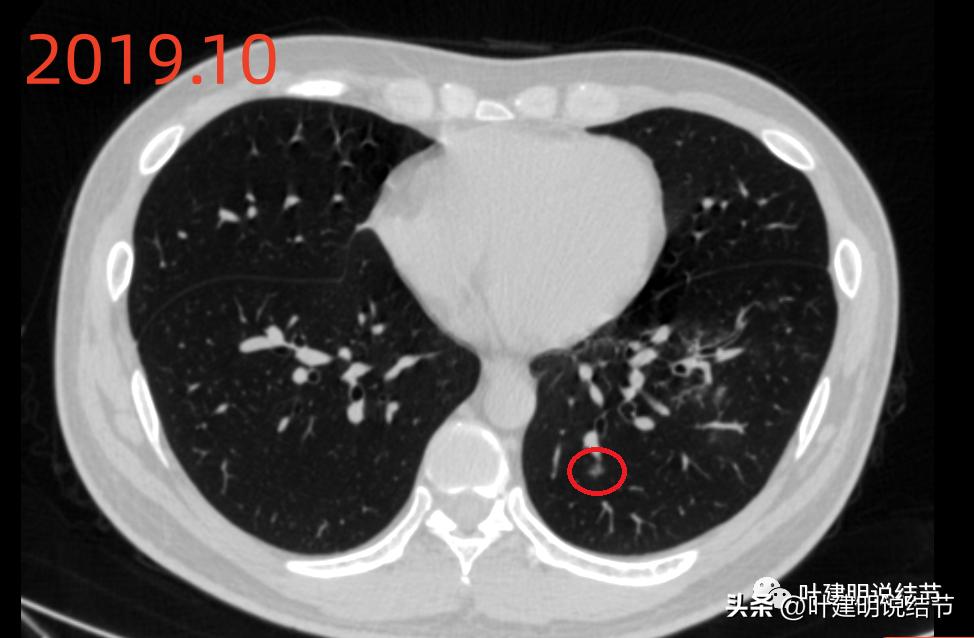

再看2019年时的影像:

病灶B当时也有,也是磨玻璃密度,轮廓清,有微小血管进入,应该仍考虑是肿瘤范畴的,只是也仍考虑不典型增生或原位癌可能性大,且前后对比无显著进展。

当时左下有肺炎。

上图是不是病灶A所在的地方?旁边 还有其他两处磨玻璃密度的结节。

上图也是当时左下的炎性区域。

先看2022年6月的片子时,感觉左下叶红色圈起来的像原位癌,桔色圈起来的像不典型增生可能性大些。但回顾2019年的片子,当时有肺炎,如绿色圈起来的范围内都是炎症性的,那时候这两个病灶也有,但红色这处当时瘤肺边界模糊点,桔色这处密度比现在感觉要高点,又结合当时炎症过,所以总体看来,桔色的考虑慢性炎性结节可能性大;红色的虽不能除外原位癌,但也无法除外炎性,至少风险应该不算高,如果再随访下也可以的。若手术,红色的要后基底段切除,桔色的要前内基底段切除,就留下外基底段与背段感觉有些孤立;若均楔形切除也是可以的,但若均是炎性,则不划算,我个人意思仍是风险不大情况下,再观察下,反正危险不大嘛!